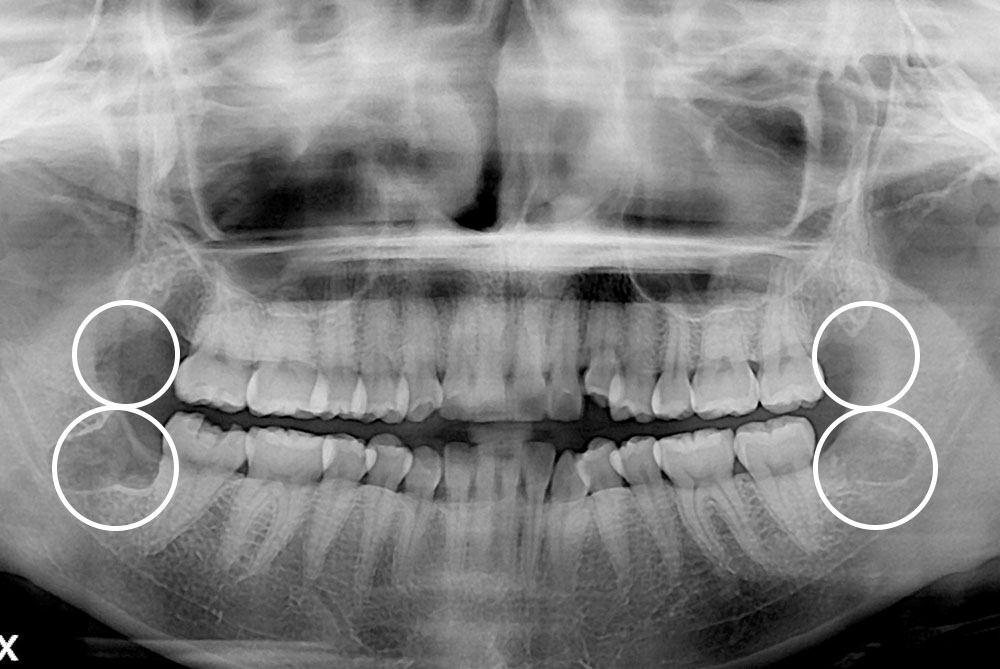

세종치과의 진심 어린 치료는 결과로 말합니다.

실제 내원하신 환자분들의 치료 전·후 사례를 확인해보세요.

모든 치료사례 전후사진은 환자분의 동의하에 촬영되었습니다.

모든사진은 동일 환자분의 전후모습을 촬영하였으며, 사진의 밝기조절 외에 임의 수정이 없음을 알려드립니다.

*수 / 시술 후 개인에 따라 결과의 차이 및 감염 등 부작용이 발생할 수 있으므로 의료진과 충분한 상담 후 결정하시길 바랍니다.